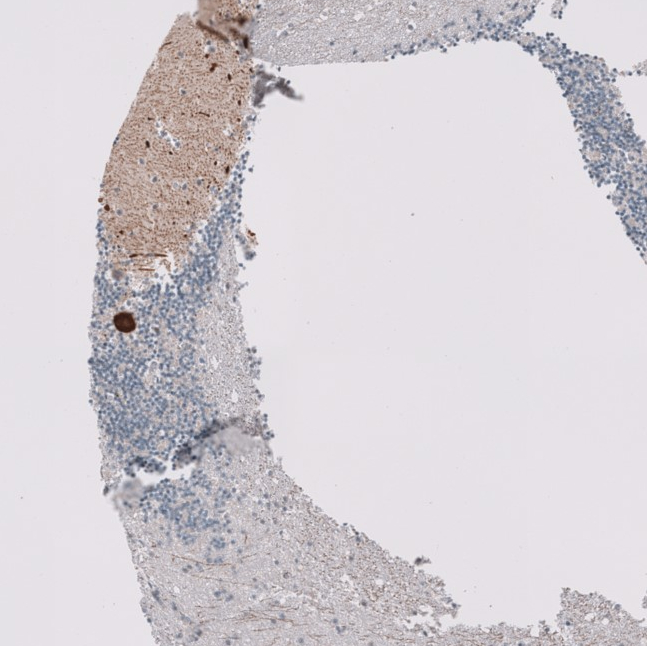

Immunohistochemical staining of human pituitary gland shows strong cytoplasmic positivity in glandular cells.